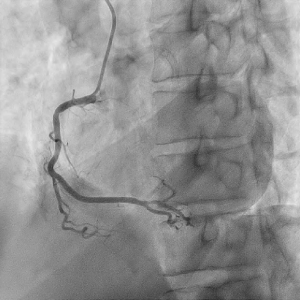

血管撮影検査

腕や足の比較的太い血管からカテーテルと呼ばれる細い管を入れ、心臓や脳、腹部の血管など選択的に挿入し、その先から造影剤を注入し、造影された血管の走行状態、病変まで撮影、治療を行います。

心臓用、頭部用、腹部用(+IVRCT)、ハイブリッド血管撮影装置の4台の装置が稼働しており、緊急検査・治療にも対応しています。